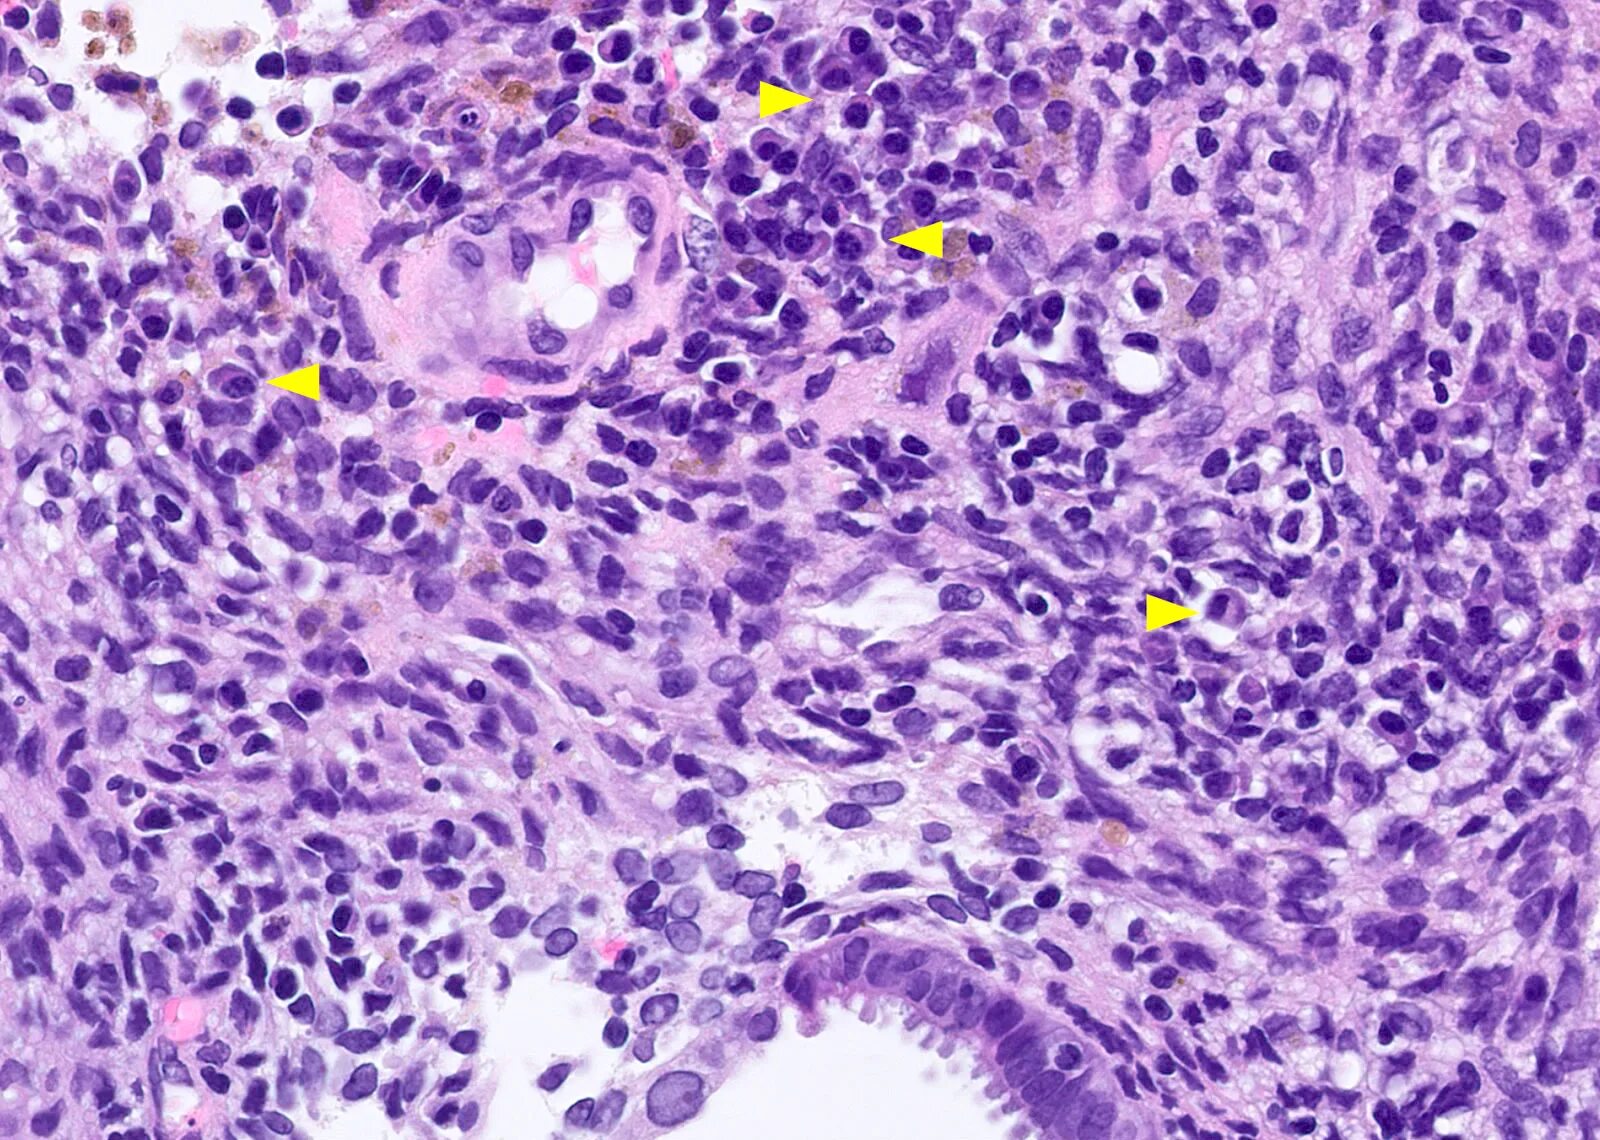

Клетка цитология гистология